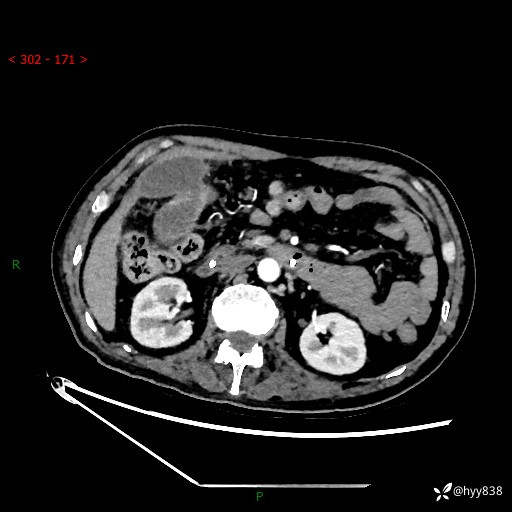

腹部CT平扫

增强